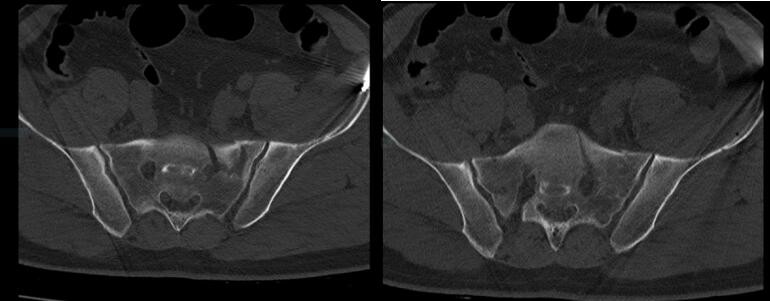

术后第二天查房时,李先生已能自主翻身:“左腿像卸掉了一块大石头!”复查CT显示:

压迫神经的碎骨完美归位

骨盆环重建误差仅1.2毫米

术后:第一次手术,骨科机器人辅助,骨盆外固定,闭合复位,骶神经孔减压。